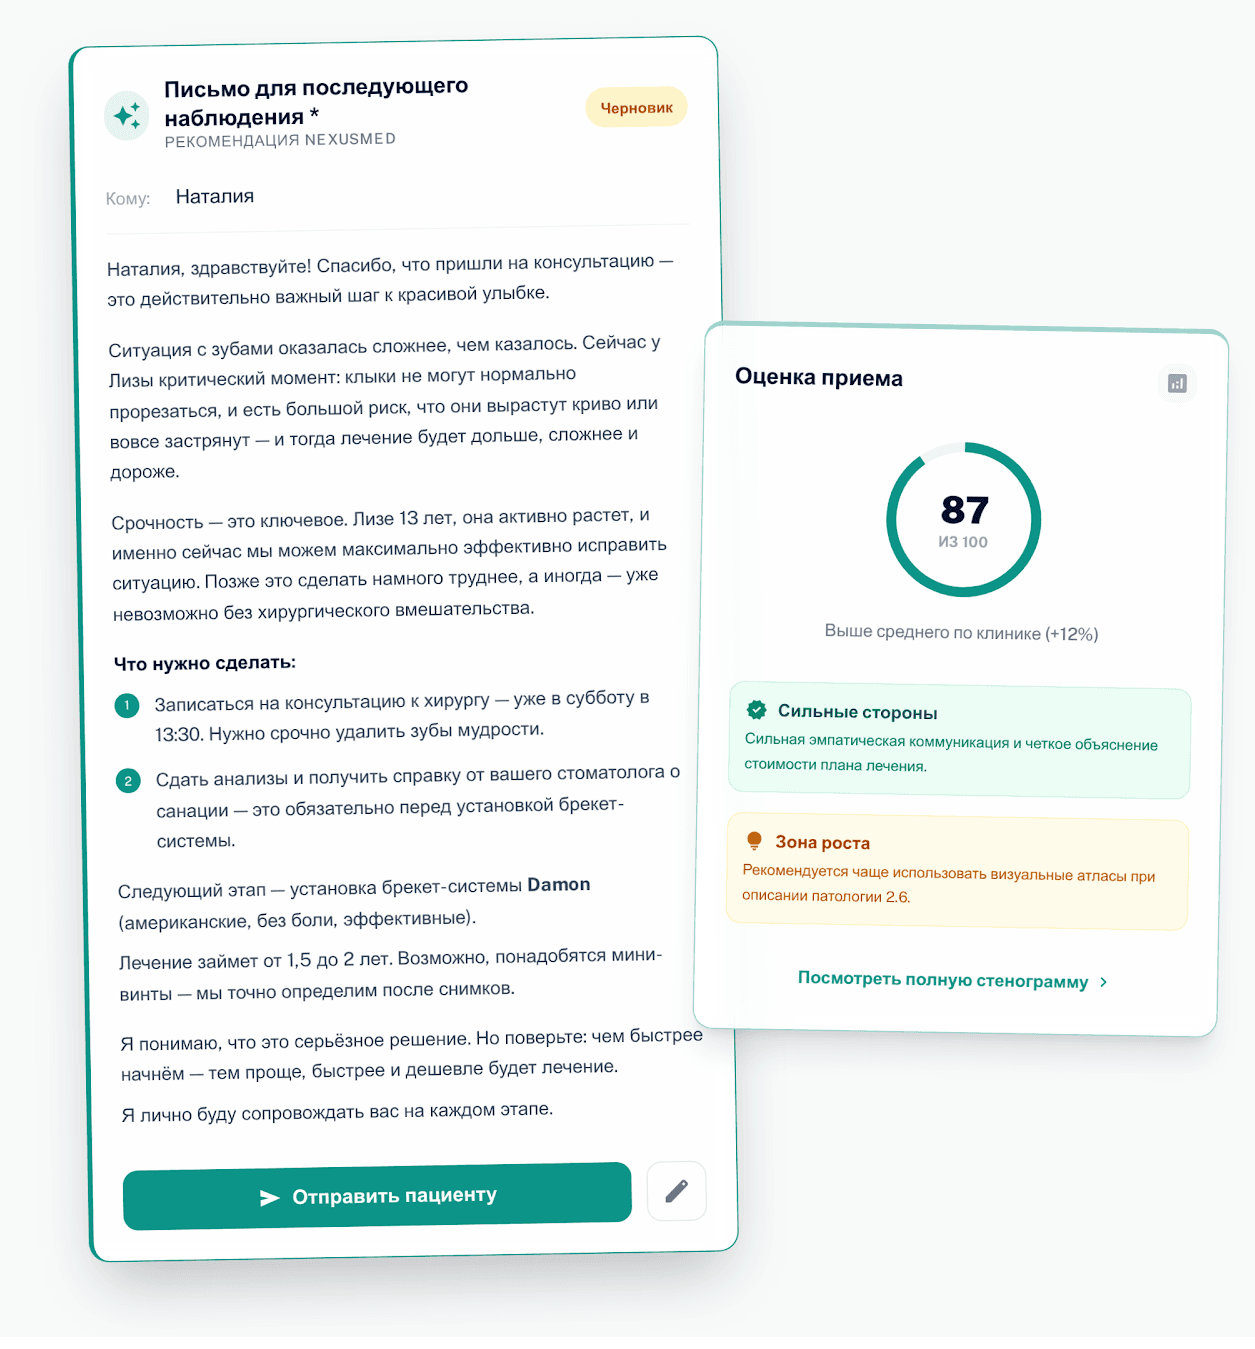

Контрольианализкоммуникации

NexusMed помогает контролировать качество консультации, снижать риск спорных ситуаций и автоматически формировать письмо пациенту сразу после приема.

100%

анализ консультации и письмо пациенту без ручной рутины